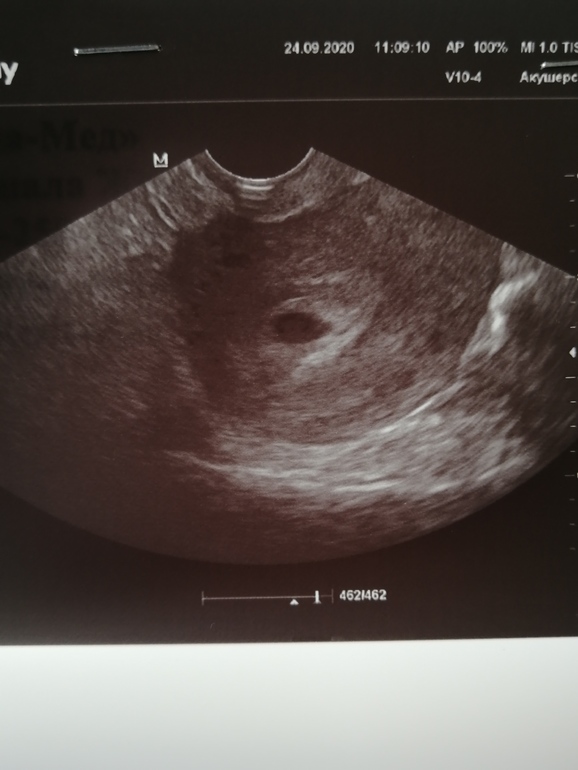

Ну что, ещё один этап пройден! Первое УЗИ!

смущает только то, что не увидели эмбрион( по последним М сейчас 5+4, а по УЗИ 4,6.

Спасибо, Ксюша! 11 мм